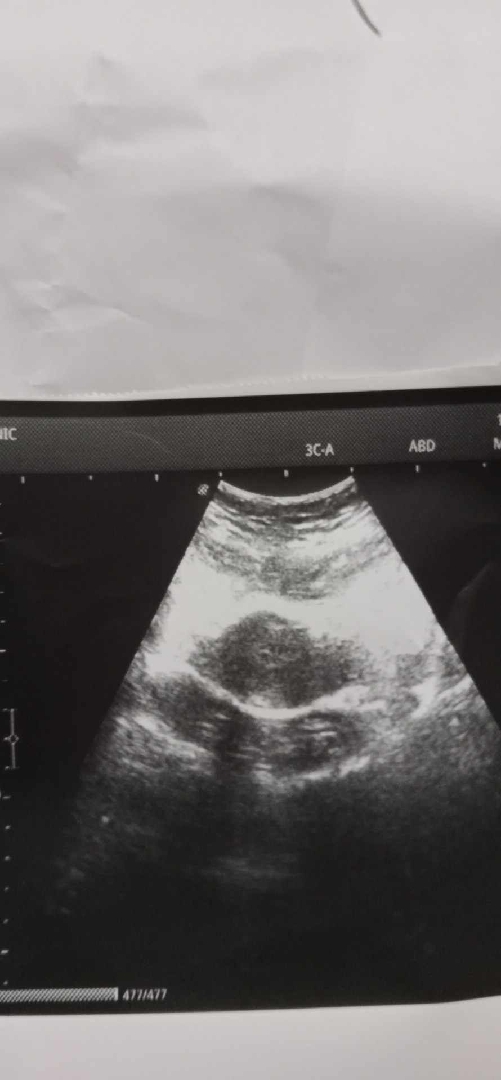

ท้อง2เดือน ภาพอัลตร้าซาวจะค่อยข้างเหนชัดมากกว่านี้ค่ะภาพนี้มองยากมากค่ะ

อยากทราบว่าแบบนี้มีสิทธิ์ท้องไหมคะ วันที่31ธันวา มีเลือดออกไม่ถึง1วันคะ ออกแค่นิดเดียวคะ

ขอบคุณคะ แบบนี้ปกติไหมคะ ซาวผ่านๆคะ